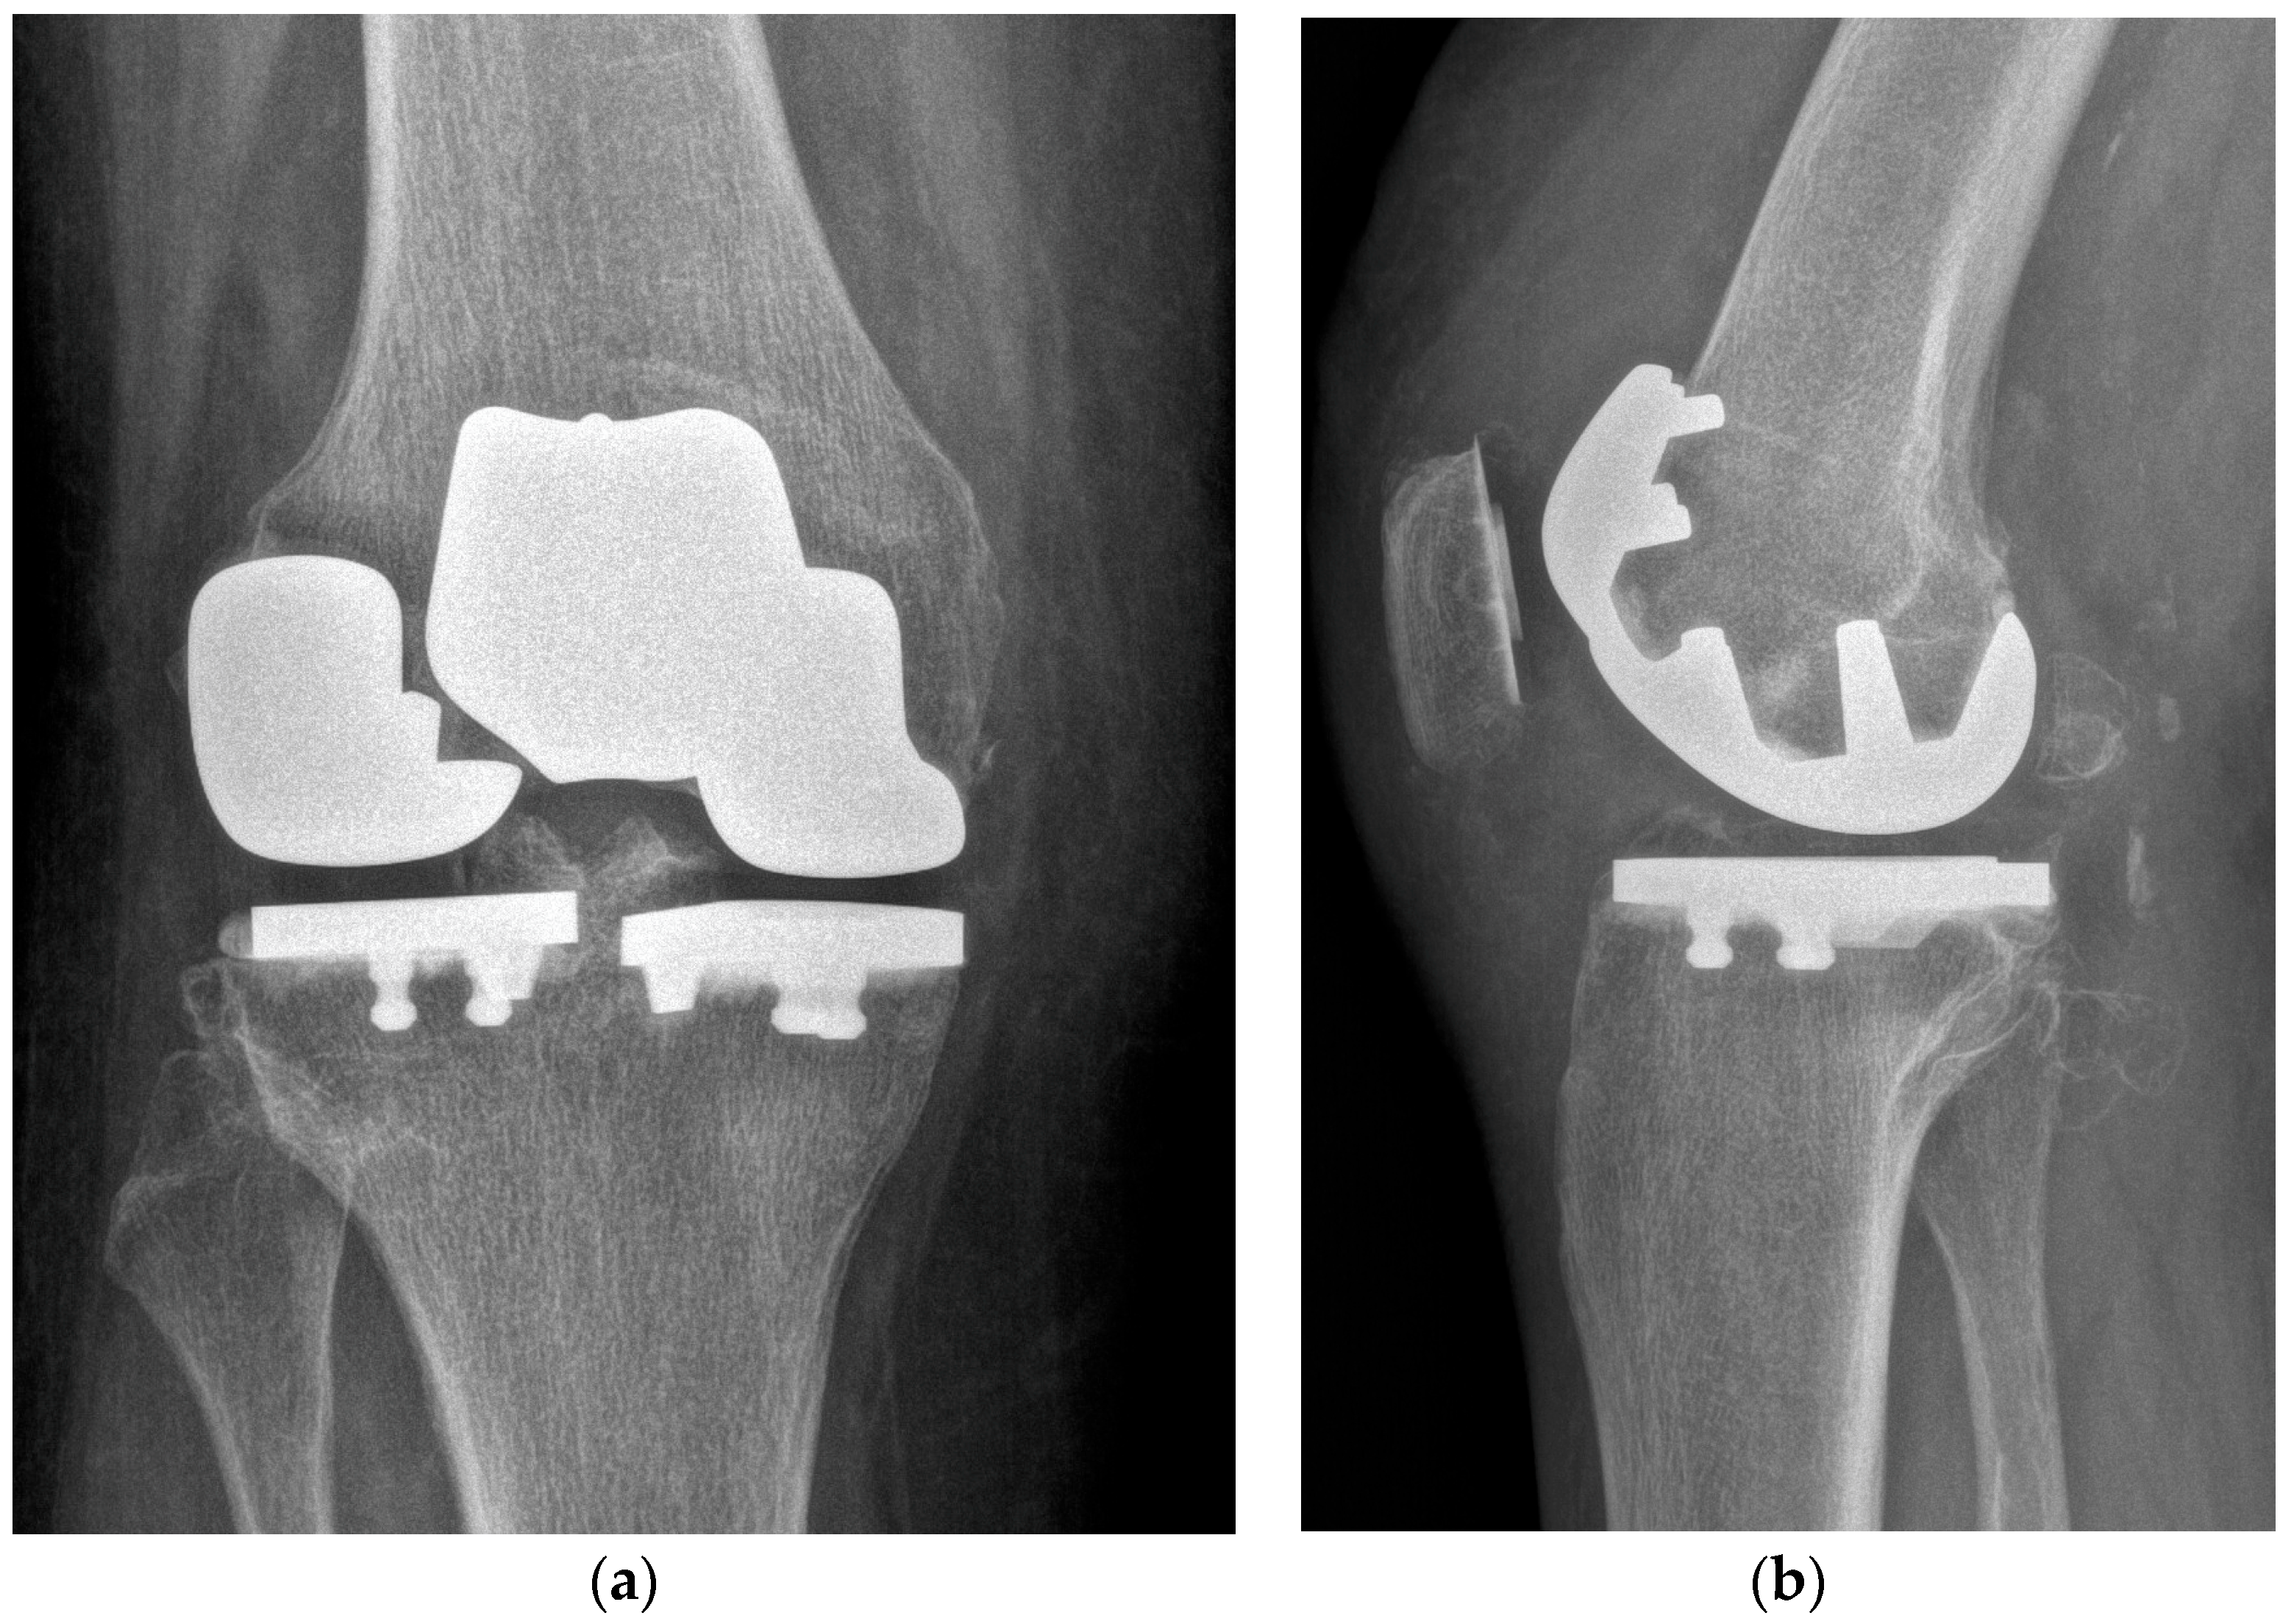

One year after surgery, the patient reported an improvement in pain and range of motion, as well as improvement in patient-reported outcomes. She gained a level 4 tegner activity scale [26] (recreational sport bicycling). At latest follow-up, the Knee Society Score (KSS) was 95, while the KSS functional score was 100. Post-operatively, the visual analogue score (VAS) was 0. X-rays at the last follow-up showed no sign of loosening or osteolysis (Figure 6).

Figure 6.

X-rays at last follow-up. (a) AP view. (b) Lateral view.

At a one-year follow-up, the patient is satisfied. She has an improvement in knee pain and function. The KSS clinical score improved from 49 pre-operatively to 95 at the last follow-up, while the KSS functional score ranged from 35 to 100. One year postoperative X-rays showed no sign of loosening or osteolysis.